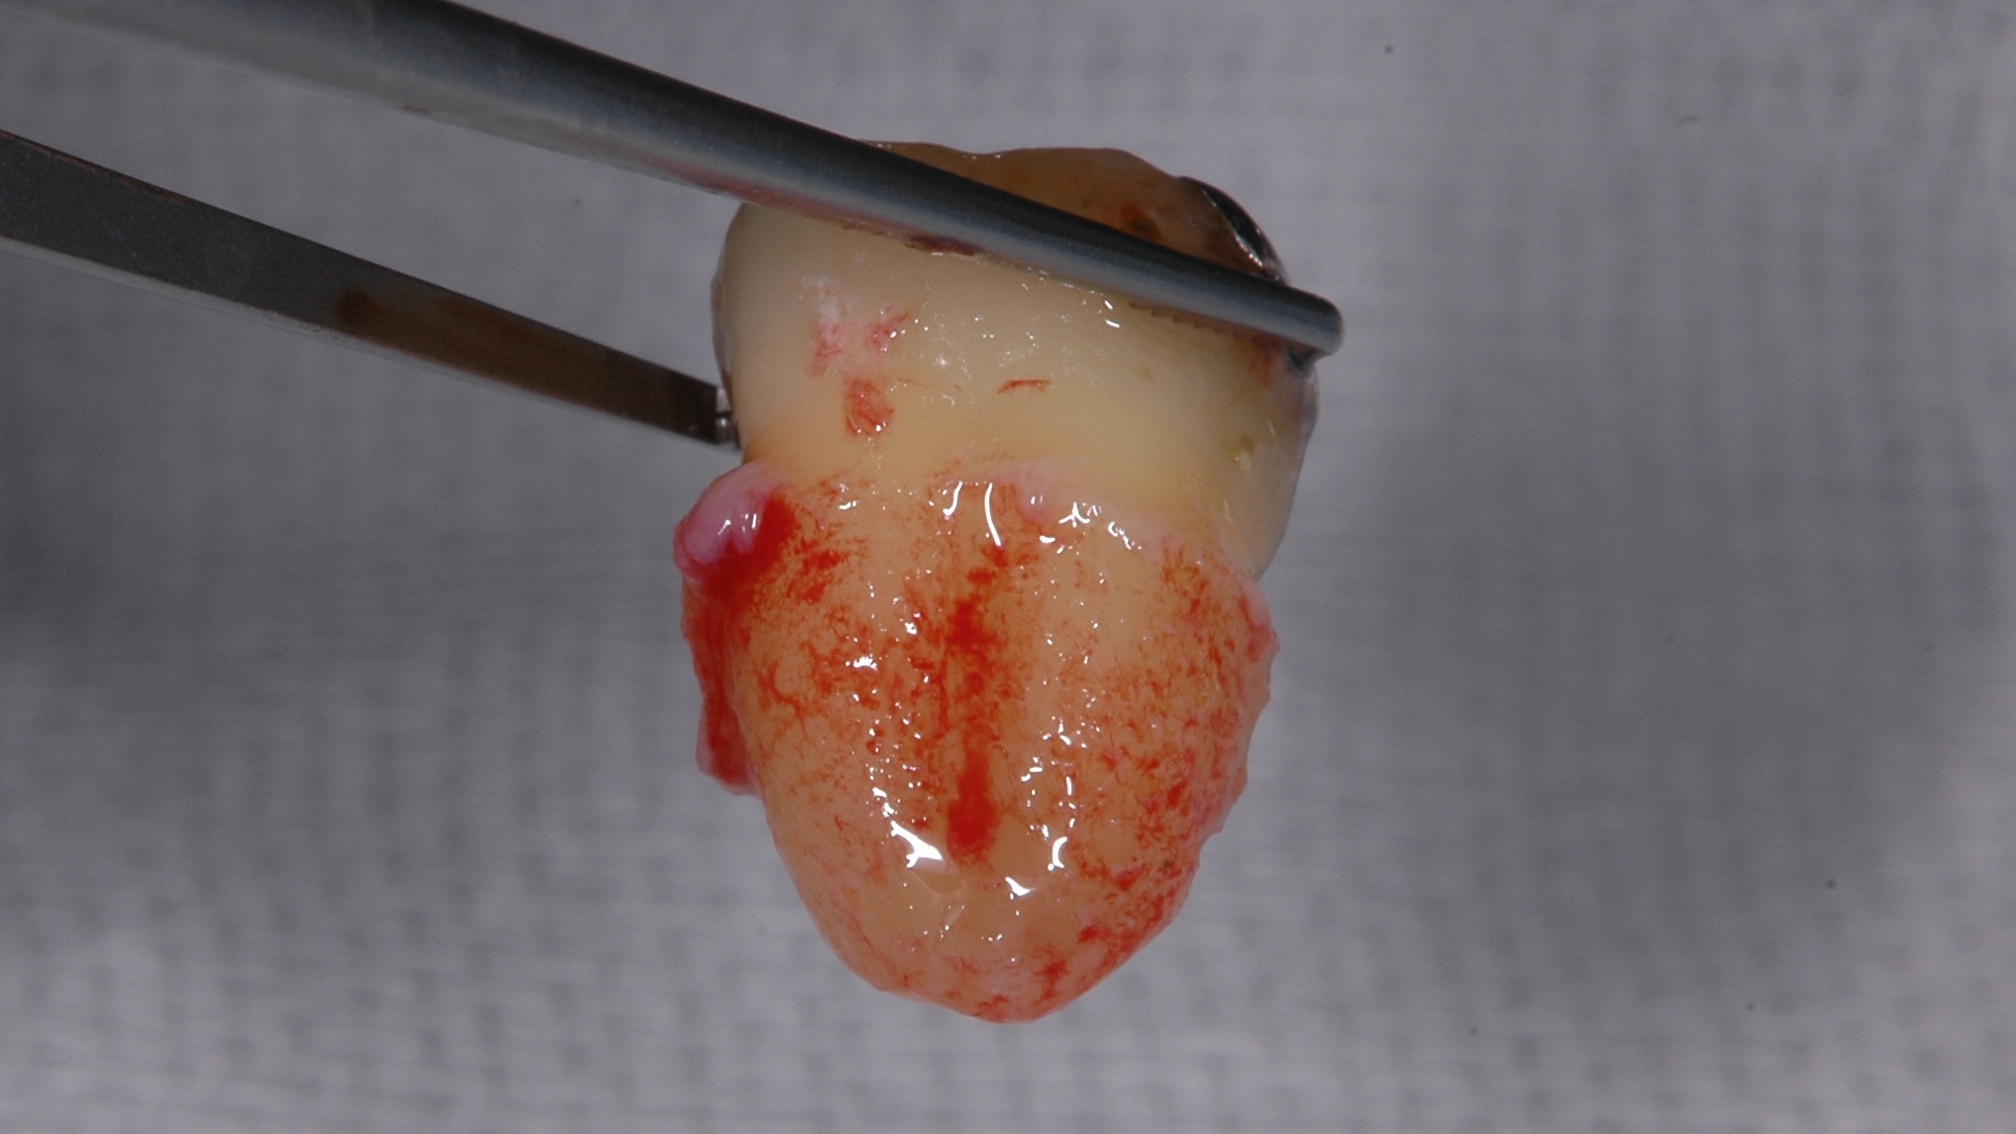

歯の移植って簡単にできるの???改変版

歯の移植って簡単にできるの???